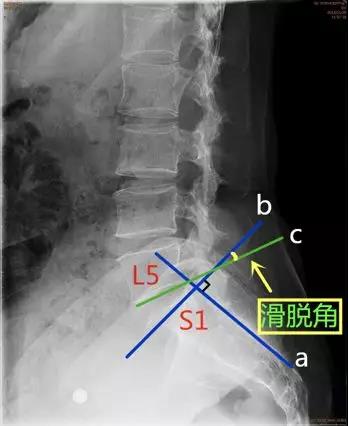

脊柱滑脱参数

- 滑脱角:S1后缘垂线与L5下终板平行线之间的夹角。正常<10°。

临床意义:>10°提示滑脱进展的风险。

- 骶骨倾(斜)角:即S1后方骶骨后缘平行线与地面垂线之间的夹角。正常值<30°。

临床意义:>30°提示滑脱进展的风险。